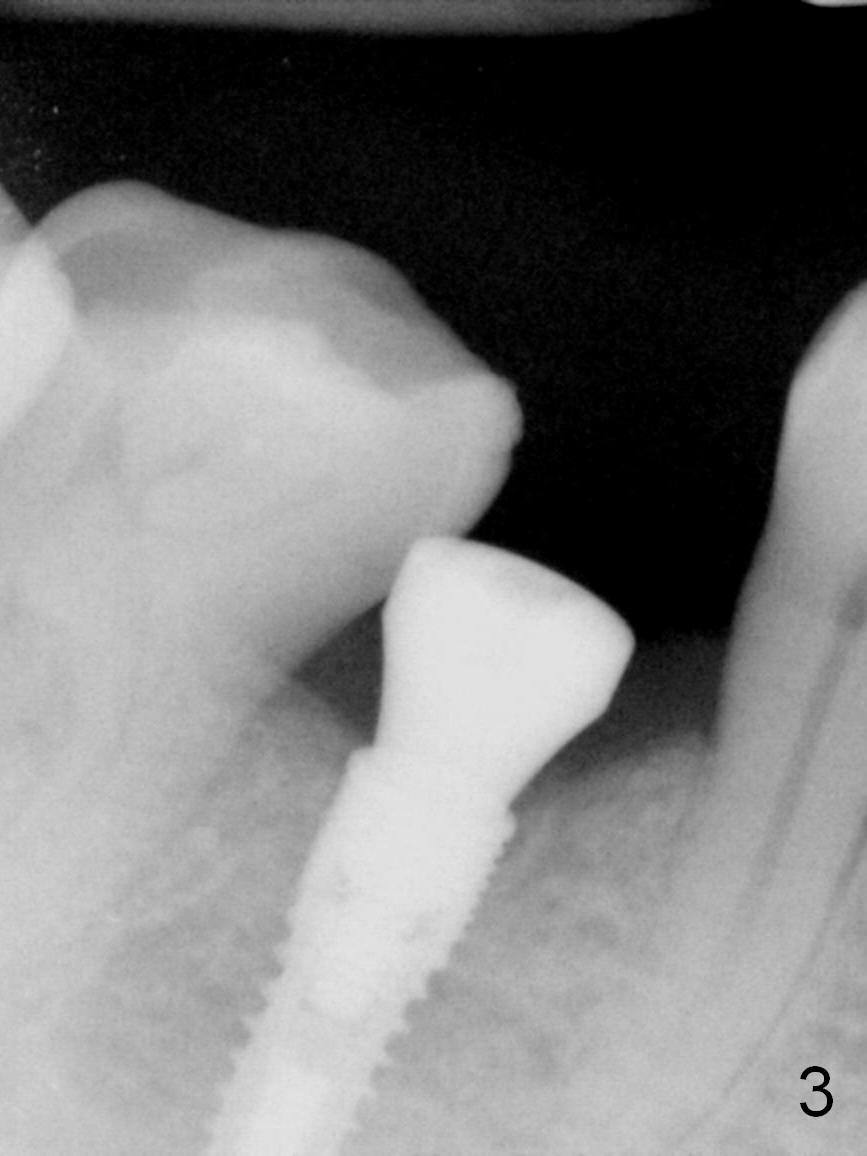

Partial edentulism with or without partial denture (especially in males) is more likely associated with implant failure than full dentition. Mr. Wang has lost several teeth (including #29, Fig.1) with secondary malocclusion, particularly supraeruption of the tooth #4. When a 3.8x10 mm submerged implant is placed with insertion torque >35 Ncm (Fig.2), an immediate provisional is selectively not placed to avoid micromovement. Instead, a healing abutment (5.2x5(3 mm) is placed immediately. For wound protection, periodontal glue and periodontal dressing are supplemented after suturing. Due to severe supraeruption of the tooth #4, the patient feels mild pain when he bites down heavily, a few hours postop. It is possible that the supraerupted tooth touches the periodontal dressing. The implant appears to be osteointegrated 4 months postop (Fig.3). A provisional is fabricated after placement of a cemented abutment (4.8x5(3) mm) to intrude the opposing tooth. There is no bone loss 2.5 years post cementation (Fig.4 CT).